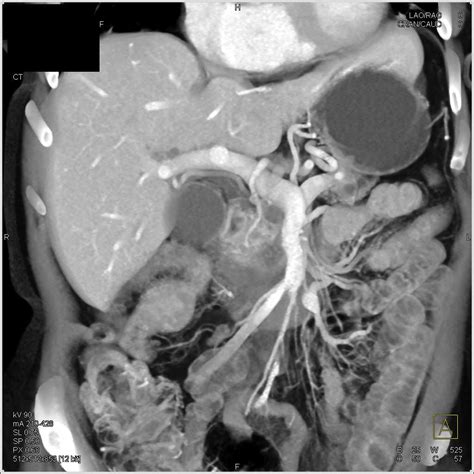

• Imaging Tests: Such as ultrasound, CT scan, or MRI to visualize the pancreas and its ducts.

These diagnostic tools help healthcare providers determine the cause of the enlarged pancreatic duct and develop an appropriate treatment plan.